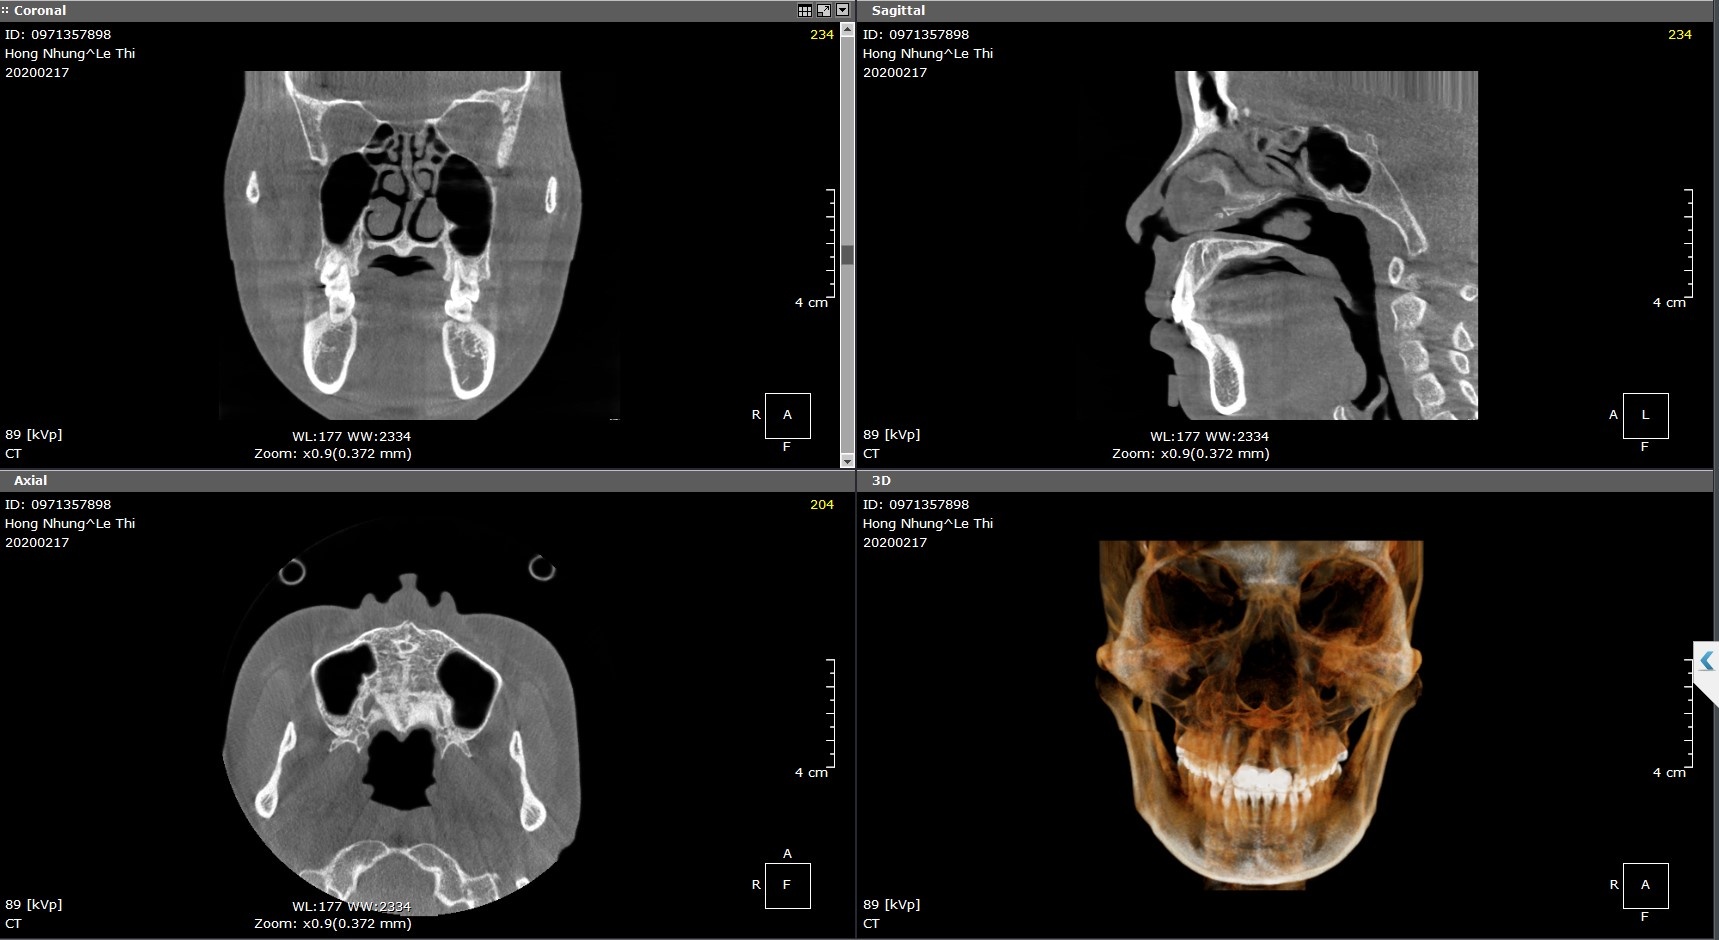

CT 3D Pro là công nghệ chẩn đoán hình ảnh trước lâm sàng, giúp bác sĩ khảo sát tình trạng cấu trúc mũi, vách ngăn, nền xương...trước phẫu thuật.

CT 3D Pro là công nghệ chẩn đoán hình ảnh 3D được ứng dụng thành công trên thế giới trong lĩnh vực thẩm mỹ, đặc biệt về phẫu thuật nha khoa và răng hàm mặt. Thông qua các dữ liệu là các hình ảnh 3D siêu thực, bác sĩ có thể chẩn đoán và xác lập phác đồ điều trị tốt nhất…

Bác sĩ Nguyễn Hoàng Nam - Giám đốc chuyên môn phòng khám nâng mũi AZ Nose, một trong những người đầu tiên ứng dụng công nghệ CT 3D Pro trong nâng mũi thẩm mỹ cho biết: “Với những chẩn đoán hình ảnh cắt lớp chi tiết, công nghệ CT 3D Pro giúp việc đánh giá các cấu trúc và hình thái giải phẫu của vùng cần chẩn đoán trở nên dễ dàng và chính xác hơn. Khách hàng cũng có cái nhìn trực quan, chân thực nhất về chính cấu trúc mũi, tình trạng mũi của mình để có thể an tâm hơn”.

Công nghệ CT 3D Pro cho phép bác sĩ khảo sát được cấu trúc mũi.

Bác sĩ Hoàng Nam cho biết thêm: “Trong nâng mũi thẩm mỹ, công nghệ CT 3D Pro cho phép bác sĩ khảo sát được cấu trúc mũi, tình trạng xương mũi, vách ngăn, xoang mũi… cũng như tầm soát các bệnh lý về mũi. Từ đó giúp bác sĩ chẩn đoán chính xác và đưa ra phương pháp nâng mũi phù hợp nhất, nâng cao hiệu quả thẩm mỹ; cũng như đưa ra các tư vấn chuyên môn về bệnh lý cho khách hàng”.

Bác sĩ tin rằng công nghệ CT 3D Pro sẽ hỗ trợ tích cực trong phẫu thuật nâng mũi và điều trị bệnh lý về mũi, đem đến cho khách hàng những dáng mũi đẹp và an toàn.